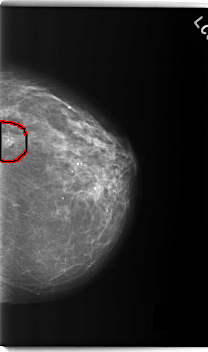

C_0218_1.RIGHT_MLO

FILE: C_0218_1.LEFT_MLO.OVERLAY

TOTAL_ABNORMALITIES 1

ABNORMALITY 1

LESION_TYPE MASS SHAPE LOBULATED MARGINS MICROLOBULATED

ASSESSMENT 5

SUBTLETY 5

PATHOLOGY MALIGNANT

TOTAL_OUTLINES 1

BOUNDARY